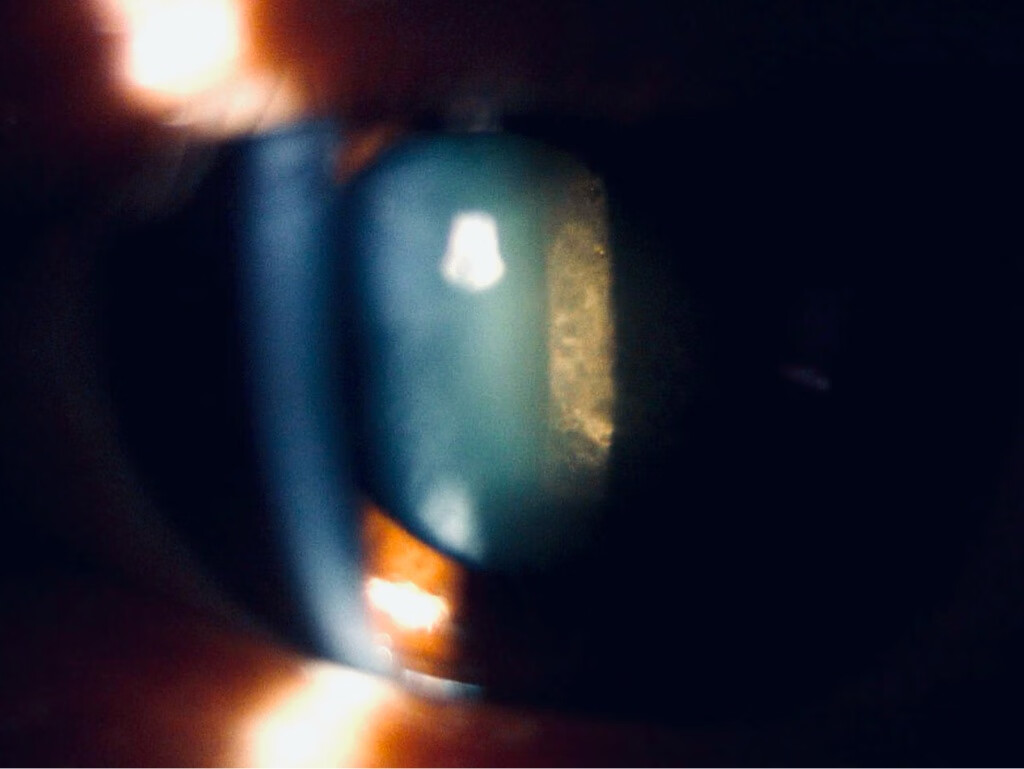

皮质性白内障

核性白内障

后囊下白内障